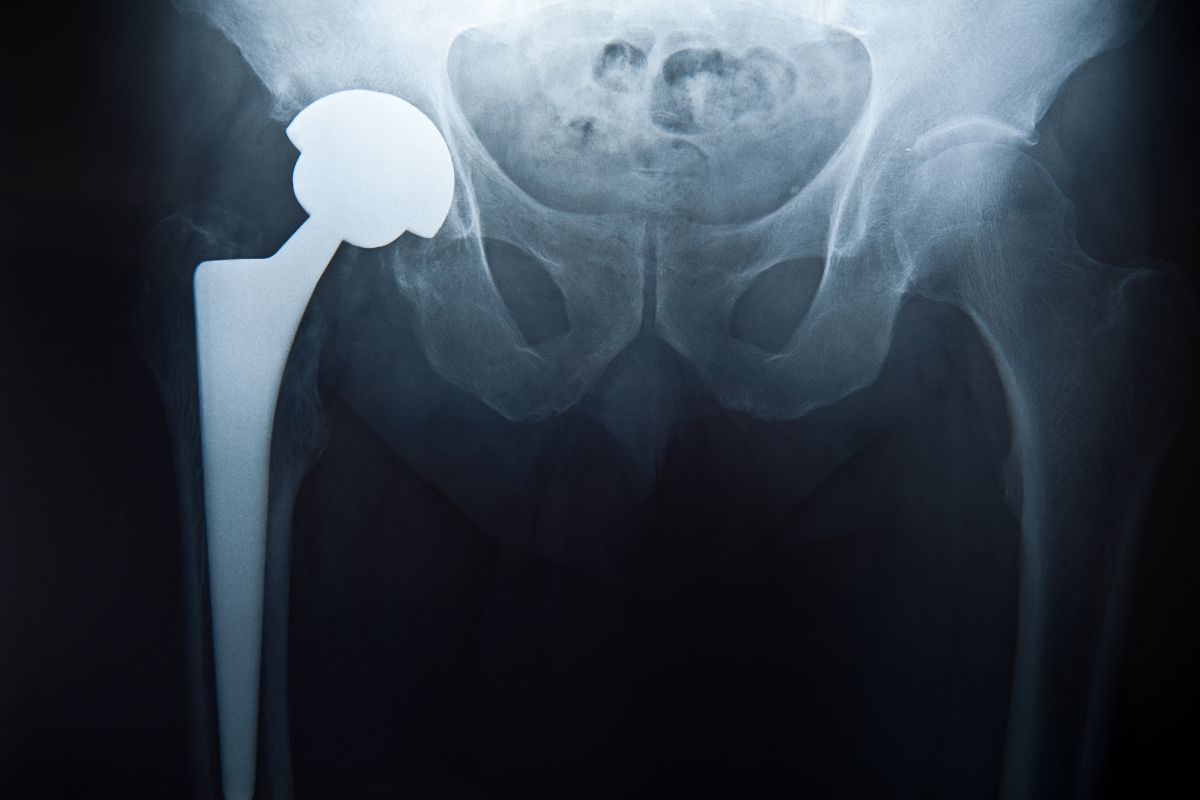

A soltura da prótese de quadril é uma complicação que ocorre quando o implante deixa de estar firmemente fixado ao osso do fêmur e/ou do acetábulo, perdendo a estabilidade necessária para o funcionamento adequado da articulação.

Em uma artroplastia bem-sucedida, a prótese se integra ao osso por meio de cimento ósseo ou por crescimento ósseo direto sobre sua superfície.

Com o passar do tempo, porém, esse vínculo pode ser comprometido por fatores mecânicos e biológicos, levando à perda progressiva da fixação.

A radiografia do quadril nos permite identificar sinais sugestivos de soltura, como linhas radiolúcidas ao redor da prótese, migração ou mudança de posição dos componentes e perda de fixação ao osso.